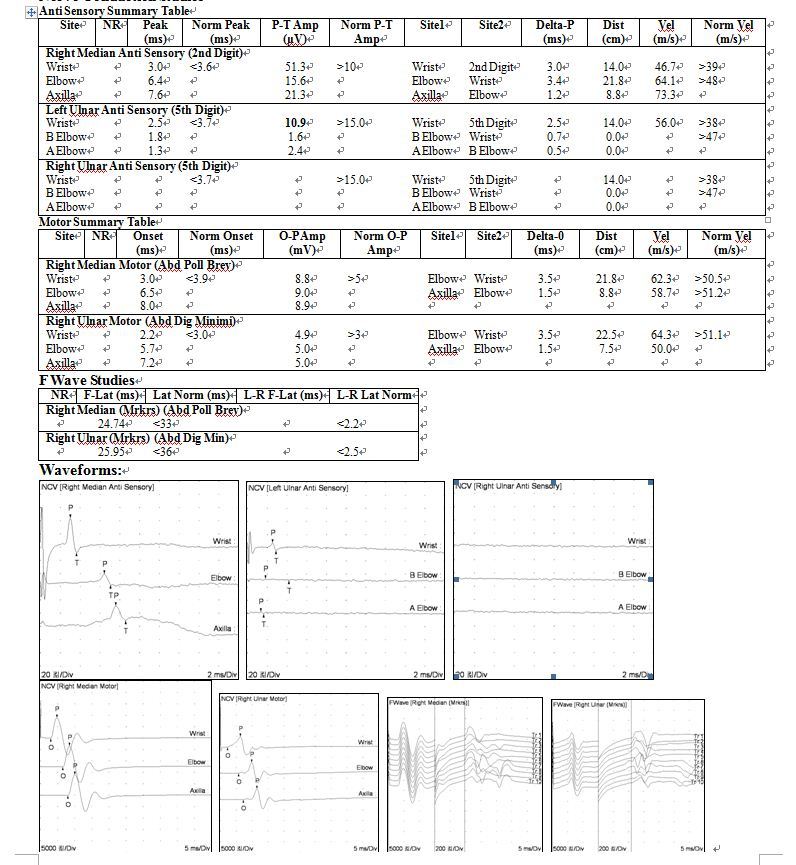

신경전도검사 우측 상지

# Ulnar N. sensory:

*Peak Latency; 경미하게 연장,

*Sensory nerve action potential(SNAP):  Elbow 상부에서 자극시 non response.

*Condution velocity: Elbow 상부에서 자극시 non response

# Ulnar N. motor:

*Terminal latency: 연장,

*Compound motor action potential(CMAP): conduction block  across the elbow.

*Condution velocity: Elbow-wrist segment 정상.Axilla-elbow segment 감소

Right Ulnar Anti Sensory (5th Digit)

Wrist

3.9

<3.7

37.6

>15.0

5th Digit

14.0

35.9

>38

B Elbow

6.4

24.3

2.5

15.5

62.0

>47

A Elbow

NR

8.5

Axilla

5.0

Motor Summary Table

Right Ulnar1 Motor (Abd Dig Minimi)

3.6

<3.0

7.6

>3

Elbow

3.7

19.0

51.4

>51.1

7.3

5.9

9.5

38.0

9.8

1.7